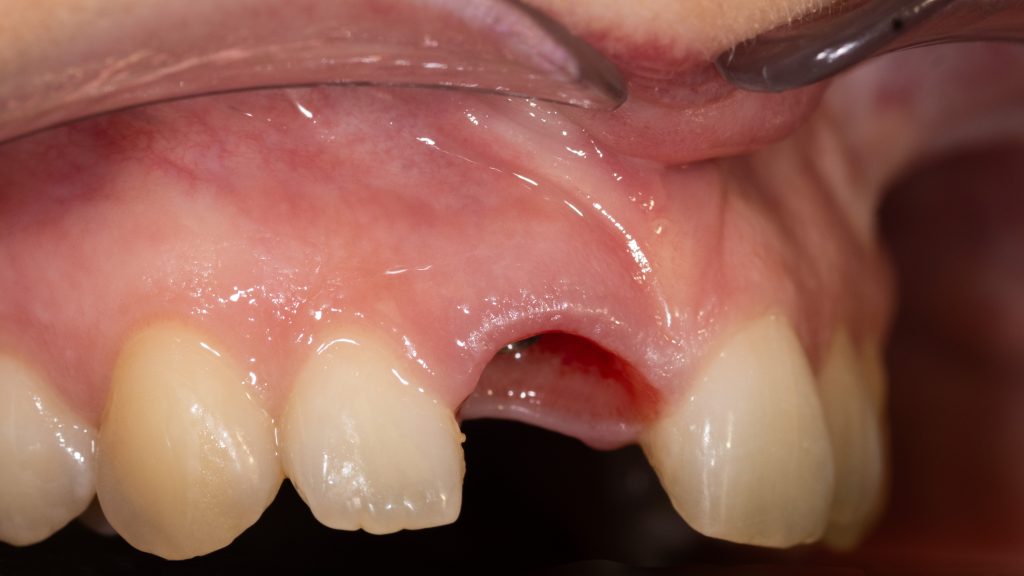

initial state